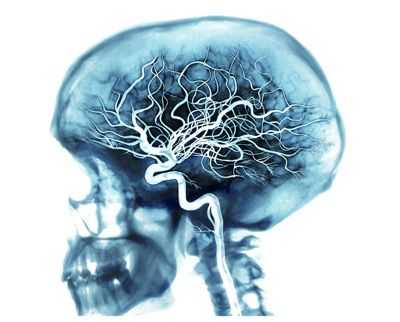

перфузия мозга на МРТ в норме (слева), при смерти мозга (в центре), при вегетативном состоянии (справа)

Дополнительные обследования не исключены из диагностических алгоритмов при смерти мозга, но и не являются строго обязательными. Их назначение — ускорить установление факта гибели мозга, особенно, в клинически сложных случаях, хотя и без них вполне можно обойтись. В России допускается проведение лишь электроэнцефалографии и ангиографии сонных и позвоночных артерий как единственно достоверных при определении признаков необратимости мозговых нарушений.